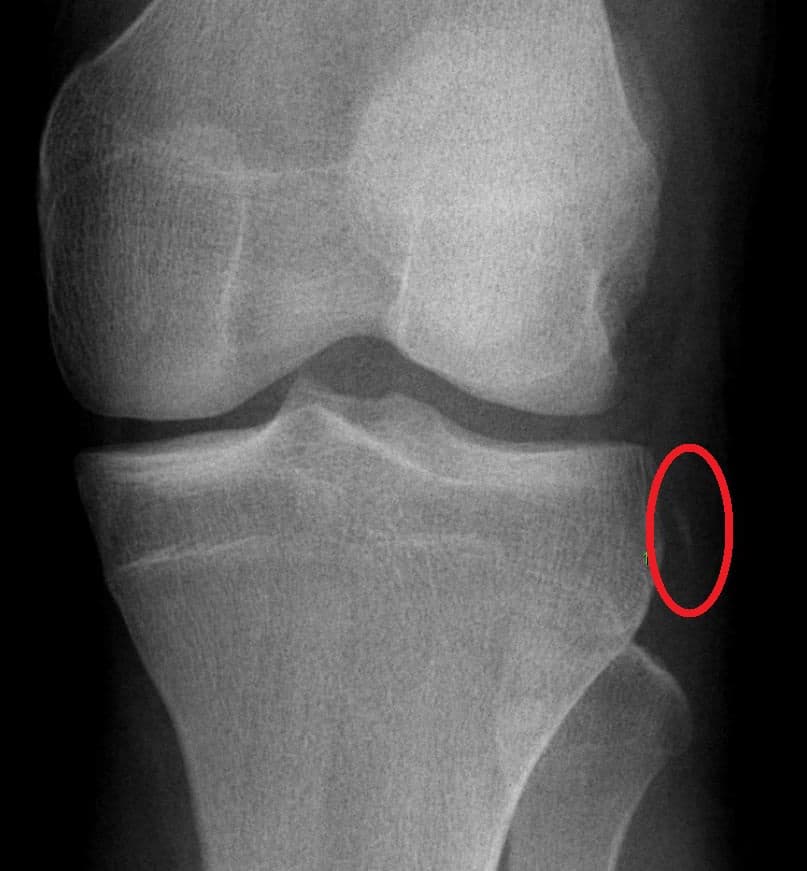

thumb|280px|Fracture de Segond La fracture de Segond est une fracture par avulsion. Elle affecte le condyle du tibia, à proximité immédiate du plateau tibial, au point d’insertion du ligament antéro-latéral (formation antéro-externe FAE). Décrite pour la première fois par le docteur Paul Segond en 1879, après une série d’observations autopsiques, la fracture de Segond est associée, dans 75 à 100 % des cas, à l’arrachement du ligament croisé antérieur (LCA) et, dans 60 à 70 % d’entre eux, à une lésion du ménisque interne. Elle peut également s’accompagner d’une lésion des structures postérieures du genou. À l'occasion de sa découverte, Segond signale l'existence d'une « bande nacrée », oubliée depuis lors, redécouverte en 2012 en France, en 2013 à l', et renommée par ses nouveaux auteurs « ». Un rare traumatisme en miroir de la fracture de Segond a également été décrit : la fracture de Segond inversée, qui se produit par avulsion de l’extrémité tibiale du ligament collatéral tibial (LCT) ou ligament latéral interne (LLI) dans l'ancienne nomenclature, accompagnée de l’arrachement du ligament croisé postérieur (LCP) et d’une lésion du ménisque interne. La fracture de Segond est le résultat caractéristique d’une rotation forcée interne du tibia sur un genou en varus. La fracture de Segond inversée est également causée par une rotation en force, mais, comme son nom l’indique, par une rotation externe et sur un valgus. D’abord considérée comme résultat exclusif d’une avulsion du tiers médian du ligament latéral externe (LLE), des recherches plus récentes ont montré que la fracture de Segond est aussi en relation avec l’insertion de la bandelette ilio-tibiale (BIT) et du ligament semi-lunaire externe. À cause de la fréquence des lésions du ligament et du ménisque qui lui sont associées, on ne peut établir le diagnostic de la fracture de Segond qu’après avoir écarté ces pathologies en tant qu’elles sont spécifiques. À la radiographie de face, la fracture de Segond présente une pastille d’os d’une taille caractéristique (voir l'image).